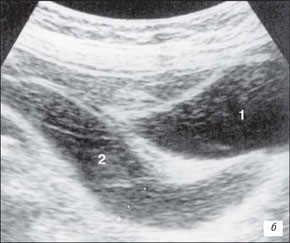

Ехограма розширення порожнинної системи нирки

А – розширення сечоводу:

Б – на тлі сечового міхура.

1 – сечовий міхур, 2 – сечовід

На даній ехограмі спостерігається: зменшення розмірів нирки на стороні поразки; циклічна зміна діаметру сечоводу у верхньому і нижньому відділах; вертикальну спрямованість сечовідно-міхурного викиду, який в нормі має напрям під кутом 30–40° по відношенню до умовної лінії, що сполучає гирла сечоводів.